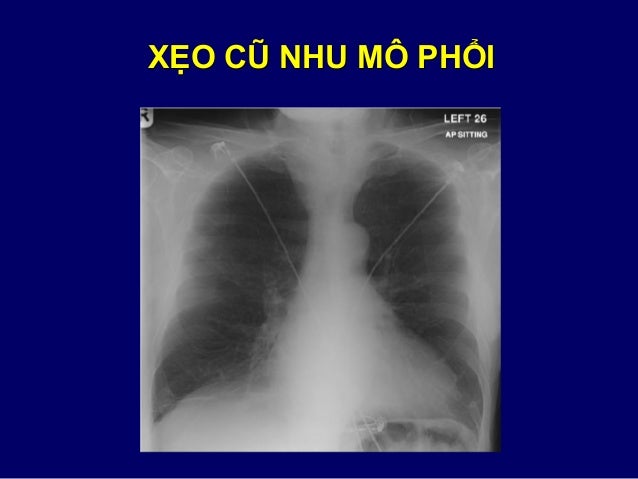

95. 95. ÁP XE

114. 114. ĐƯỜNG MỜ CÁC NGUYÊN NHÂN  Suy tim trái  Tuổi già  Lan tràn ung thư theo đường bạch mạch  Xẹo cũ nhu mô phổi  Xơ hóa phổi  Xẹp phế nang – tiểu phế quản tận  Xẹp phổi dưới phân thùy

115. 115. SUY TIM TRÁI

125. 125. NGUYÊN NHÂN XƠ PHỔI Thùy trên Thùy giữa Thùy dưới  Lao  Viêm phế nang dị ứng ngoại sinh mạn tính  Xạ trị  Viêm cột sống cứng khớp  Xơ phổi lớn tiến triển tự miễn  Nhiễm Histoplasmosis  Sarcoidosis  Viêm phổi mô kẽ không do tác nhân vi sinh vật  Xơ phổi do tiếp xúc Asbestos  Xơ phổi do thuốc (thường gặp nhất)

126. 126. THÔNG ĐIỆP CẦN NHỚ VỀ TỔN THƯƠNG ĐƯỜNG MỜ  Là biểu hiện bệnh tại đường thở, bạch mạch, tĩnh mạch và mô kẽ phổi  So sánh với phim cũ rất có ích để xác định nguyên nhân  Bệnh khác nhau  đường mờ khác nhau  Giảm thể tích phổi là triệu chứng quan trọng trong xơ phổi